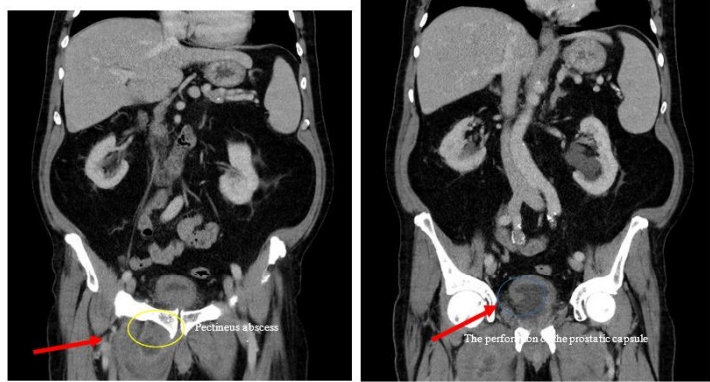

A 74-year-old Caucasian man came to the emergency department with pain in adduction on the inner side of the right thigh and on the fever of 38,2° C. In its medical history has shown that ventricular extrasystole, high-grade aortic valve stenosis and transurethral prostate resection 2 weeks ago. He had neither immunosuppressive disease nor medication. He does not smoke, nor did his family history contribute. On physical examination, he had no symptoms except pain on palpation and adduction in the upper right inner thigh. Laboratory has demonstrated that a high leukocyte count of 13.41 x 109/l. The patient's C-reactive protein was elevated at 95.87 mg/l, the culture of the urine was sterile. A computer tomography was performed, which revealed that an inflammation of the pectineus muscle adjacent to approximately 2,5 cm abscess (Figure 1). This abscess area was also found to be associated with the prostatic capsule (Figure 2).

FIGURE 1:     Abdominopelvic CT scan revealed that a 2,5 cm pectineus abscess area [(a) yellow circle] and a perforation of the prostatic capsule [(b) blue circle].